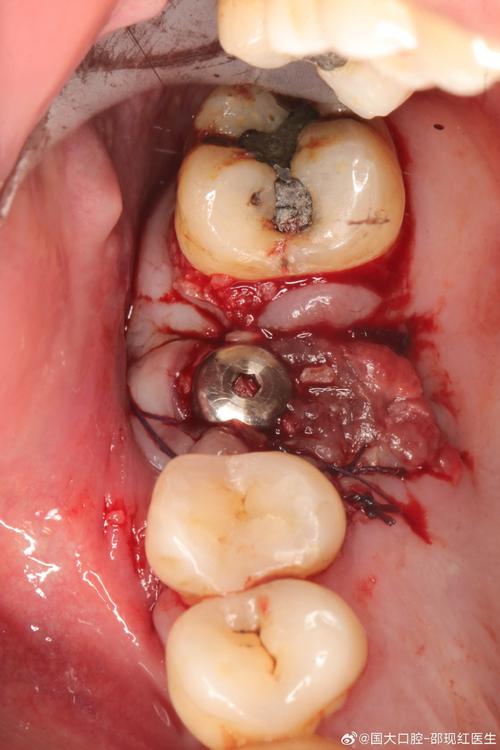

- 骨吸收严重或种植体松动:需手术干预,包括翻瓣清创、植骨(重建骨量),必要时取出种植体,待骨愈合3-6个月后重新植入;